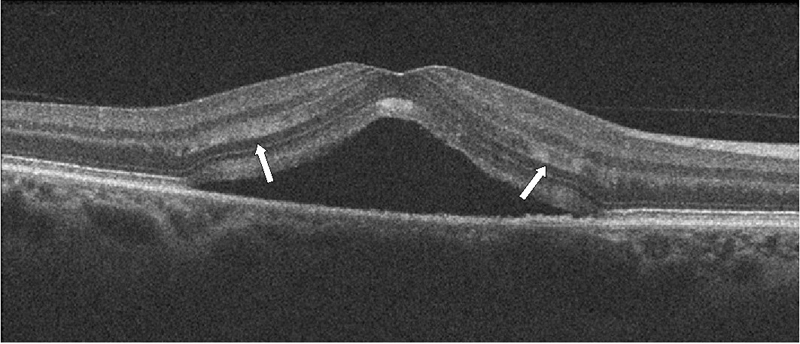

La tomografía en las formas agudas muestra un desprendimiento neurosensorial. A diferencia de otras enfermedades, como la degeneración macular, en la CSC suele existir una conservación parcial de la retina externa y del epitelio pigmentario, y se aprecia un alongamiento moderado de los segmentos externos de los fotorreceptores, la desaparición de la capa elipsoide, una disminución del grosor de la capa nuclear externa y normalidad en la membrana limitante externa (

Figura 2 y

Figura 3).

Figura 2. Hallazgos en la coroidorretinopatía serosa central aguda. Se aprecia un desprendimiento neurosensorial, con disminución de la capa nuclear externa. La membrana limitante externa aparece conservada. Existe un alargamiento de los fotorreceptores y una alteración de la capa elipsoide (flechas blancas).